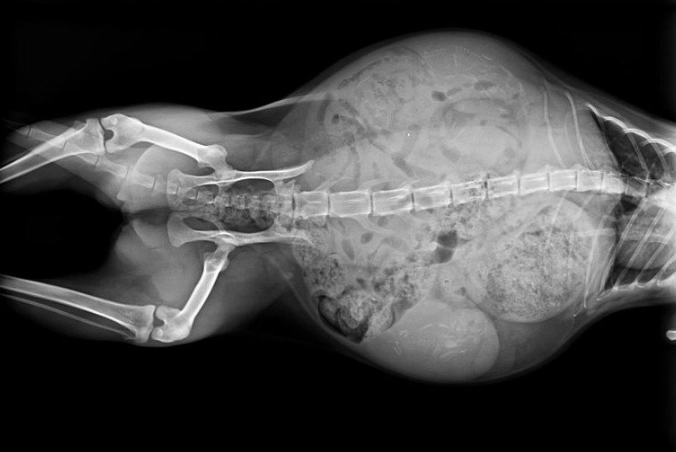

Is an X-ray or ultrasound safe?

Yes, when performed by a veterinarian. Ultrasound is typically used earlier (after 21 days) to confirm pregnancy and viability. X-rays are used later (after day 45, when fetal skeletons mineralize) to get a more accurate kitten count and check positioning. Vets use minimal exposure to keep it safe.